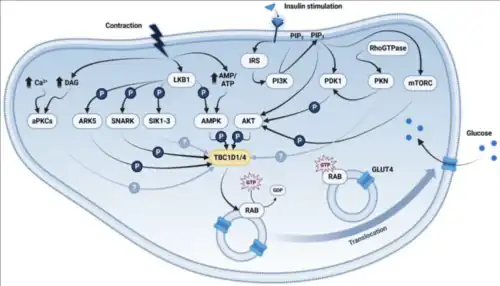

The mechanism for GLUT4 is an example of a cascade effect, where binding of a ligand to a membrane receptor amplifies the signal and causes a cellular response. In this case, insulin binds to the insulin receptor in its dimeric form and activates the receptor's tyrosine-kinase domain. The receptor then recruits Insulin Receptor Substrate, or IRS-1, which binds the enzyme PI-3 kinase. PI-3 kinase converts the membrane lipid PIP2 to PIP3. PIP3 is specifically recognized by PKB (protein kinase B) and by PDK1, which can phosphorylate and activate PKB. Once phosphorylated, PKB is in its active form and phosphorylates TBC1D4, which inhibits the GTPase-activating domain associated with TBC1D4, allowing for Rab protein to change from its GDP to GTP bound state. Inhibition of the GTPase-activating domain leaves proteins next in the cascade in their active form, and stimulates GLUT4 to be expressed on the plasma membrane.[30]

Muscle contraction stimulates muscle cells to translocate GLUT4 receptors to their surfaces. This is especially true in cardiac muscle, where continuous contraction increases the rate of GLUT4 translocation; but is observed to a lesser extent in increased skeletal muscle contraction.[35] In skeletal muscle, muscle contractions substantially increase GLUT4 translocation,[36] which is regulated by RAC1[37][38] and AMP-activated protein kinase (AMPK).[39] Contraction-induced glucose uptake involves the phosphorylation of RabGaps, TBC1D1 and TBC1D4, by AMPK and other kinases such as SNARK.[40][41] This mechanism remains functional in insulin-resistant states, establishing the muscle-contraction pathway's independence from insulin stimulation.[41] The figure to the right demonstrates how insulin- and contraction-stimulated GLUT4 translocation differ but ultimately converge on TBC1D1/4. Phosphorylation of TBC1D1/4 inactivates it, allowing Rab proteins to load GTP and directly participate in the trafficking of GLUT4 to the membrane.[15]

AMPK plays a crucial role in the contraction pathway.[42] ATP is known as an energy-sensing enzyme, as it's highly responsive to an increase in the AMP to ATP ratio.[42] ATP is hydrolyzed to ADP during muscle contraction by actomyosin ATPase.[43] Adenylate kinase subsequently converts ADP through the following reaction: 2ADP→ATP+AMP.[43] This ensures rapid replenishment of ATP, while increasing AMP concentration.[43] ATP competes with AMP for coupling to the AMPK binding domain and thus inhibits AMPK activity, particularly when the muscle is at rest and ATP concentration is high.[42] AMP has a much stronger affinity for the binding domain (known as the Bateman domain) of AMPK, and will thus out-compete ATP as AMP concentration increases.[42] This ultimately results in the phosphorylation and activation of AMPK by LKB1[44] and triggers a cascade of signaling events driven by AMPK, leading to the translocation of GLUT4.[15]